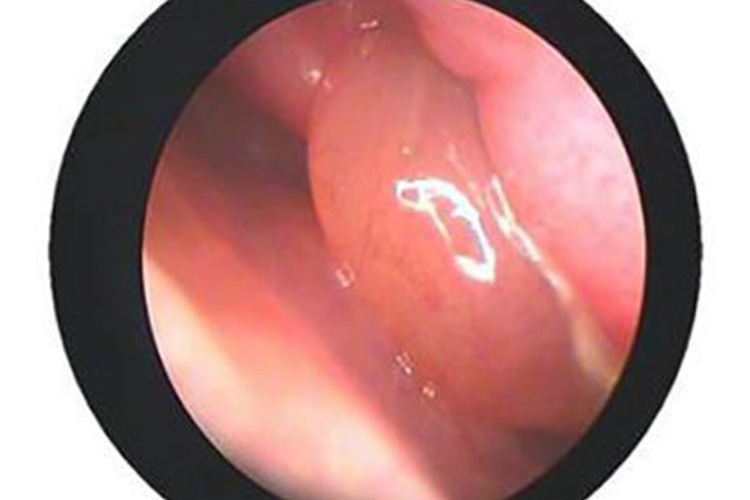

鼻窦炎时患侧鼻腔发生持续性鼻塞,鼻甲发生肿胀,鼻腔内可出现大量脓性或黏脓性鼻涕,难以擤尽,脓涕中可带有少许血丝,伴有头痛或局部疼痛。

鼻炎初期表现鼻内干燥、灼热感、痒感、酸痛不适和喷嚏;继而出现鼻塞、水样鼻涕、嗅觉减退和闭塞性鼻音。继发细菌感染后,鼻涕变为脓性。可伴有耳部闷胀不适或堵塞感,部分患者伴有耳鸣或听力下降。全身症状因个体而异,轻重不一。初起时多数表现为全身不适、倦怠、头痛或发热症状。